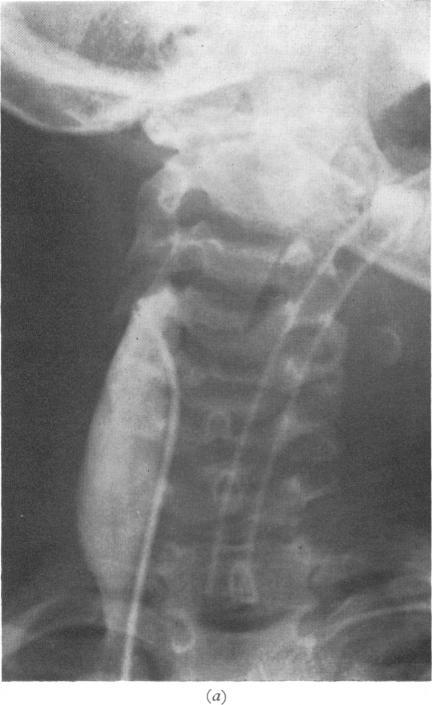

The 'grey toddler'. Chloramphenicol toxicity.

Arch Dis Child. 1974 Mar;49(3):235-7. doi: 10.1136/adc.49.3.235.

https://cdn.ncbi.nlm.nih.gov/pmc/blobs/2db4/1648692/86e90222acfb/archdisch00855-0077-b.jpg

https://cdn.ncbi.nlm.nih.gov/pmc/blobs/2db4/1648692/00cd3cb2072e/archdisch00855-0077-a.jpg